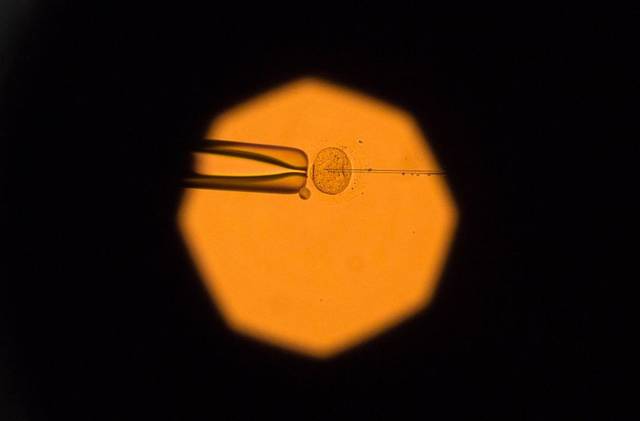

图 | 电子显微镜下的卵母细胞。(来源:彭博社)